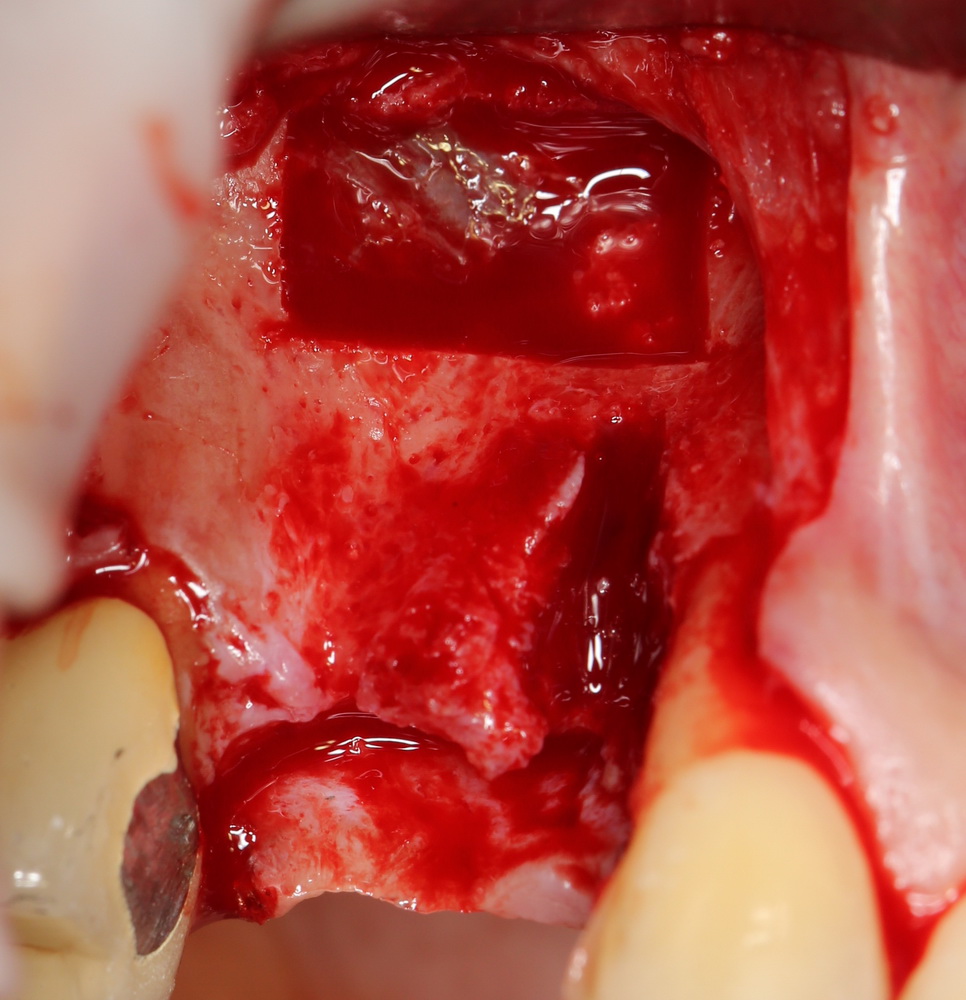

И вроде бы, все неплохо, но когда мы скелетируем костную ткань, то видим следующее:

Можно ли поставить импланты? Теоретически, если использовать импланты диаметром 3,0 мм — вполне возможно. Но как это будет потом выглядеть? Большие коронки на тоненьких имплантах с тонкой десной? А если эти зубы еще попадают в эстетически значимую зону и видны при улыбке? А если это еще и девушка, которая собирается замуж? И вот тут встает вопрос о размерах и позиционировании имплантов, который тянет за собой вопрос об остеопластике.

Поэтому мы начинаем с синуслифтинга:

Полученная костная пластинка заведомо больше необходимого окна. Мы потом используем ее при остеопластике. Убираем ее, видим слизистую оболочку верхнечелюстной пазухи, которую нам нужно приподнять:

приподнимаем и создаем субантральное пространство: